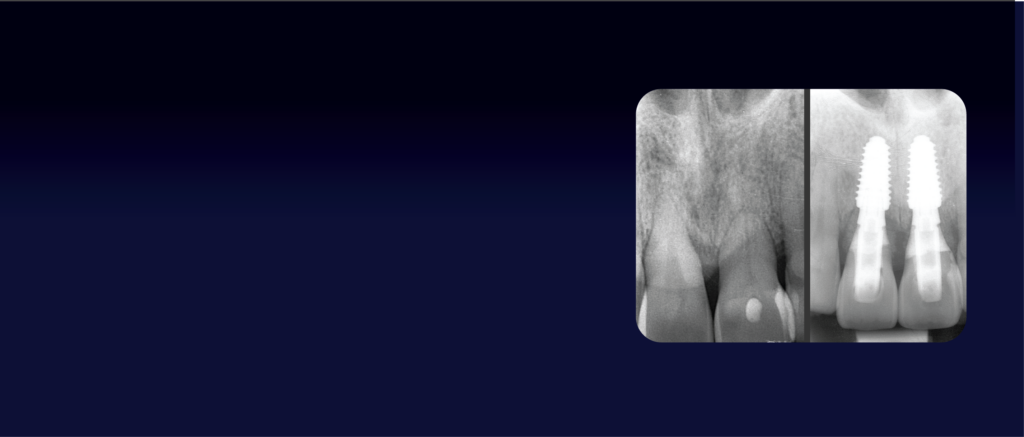

La cirugía guiada se ha convertido en una herramienta clave para afrontar tratamientos implantológicos con mayor precisión, control y predictibilidad, especialmente en casos complejos y protocolos de carga inmediata. Su correcta aplicación permite minimizar errores, optimizar tiempos quirúrgicos y mejorar significativamente los resultados clínicos.

Este curso está diseñado para formar al profesional en el dominio real del flujo digital aplicado a la carga inmediata, combinando planificación avanzada, toma de decisiones clínicas y práctica aplicada. El objetivo es que el alumno sea capaz de planificar y ejecutar tratamientos implantológicos complejos con mayor seguridad, integrando la carga inmediata de forma fiable y predecible en su práctica diaria.